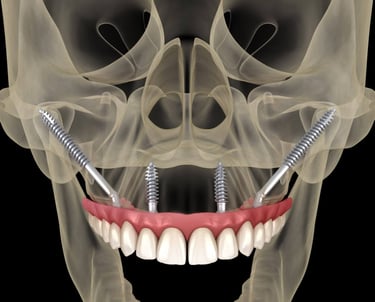

IMPLANTY ZYGOMATYCZNE

W przypadku pacjentów z dużym zanikiem kości, optymalnym rozwiązaniem są implanty zygomatyczne (jarzmowe). Implanty jarzmowe różnią się od tradycyjnych implantów dentystycznych tym, że są zamocowane w kości jarzmowej (kości policzkowej), a nie w szczęce. Mają inny, wydłużony kształt i wymagają bardziej złożonej procedury. Jest to wspaniała alternatywa dla pacjentów, która radykalnie skraca czas rekonstrukcji uzębienia i umożliwia pacjentom cierpiącym na ciężką utratę kości szczęki powrót do normalnej jakości życia. W znakomitej ilości przypadków zęby mocuje się już w dniu zabiegu. Tym sposobem pacjent unika wielomiesięcznego cyklu inwazyjnych procedur przeszczepu kości w celu stworzenia podłoża dla konwencjonalnych implantów.

Przed umieszczeniem implantów jarzmowych wykonamy badanie TK, dzięki któremu specjalista implantolog precyzyjnie zaplanuje rozmieszczenie implantów. Następnym krokiem jest stworzenie strukturalnego modelu szczęki (tzw. szablonu), który pozwoli ocenić kształt Twojej kości policzkowej oraz szczęki i dokładnie przeprowadzić operację. Zabieg wszczepienia implantów jarzmowych zazwyczaj odbywa się w głębokim znieczuleniu, więc nie będziesz odczuwać bólu ani dyskomfortu. Nad przebiegiem operacji czuwać będzie zespół wyspecjalizowanych medyków z chirurgiem implantologiem i anestezjologiem na czele.

Most na implantach zamocujemy najprawdopodobniej tego samego dnia. Okres rekonwalescencji trwa tylko kilka tygodni i nie wiąże się z bólem czy koniecznością wycofania z życia. Bardzo szybko zaczynasz funkcjonować jakbyś miał(a) własne naturalne zęby.